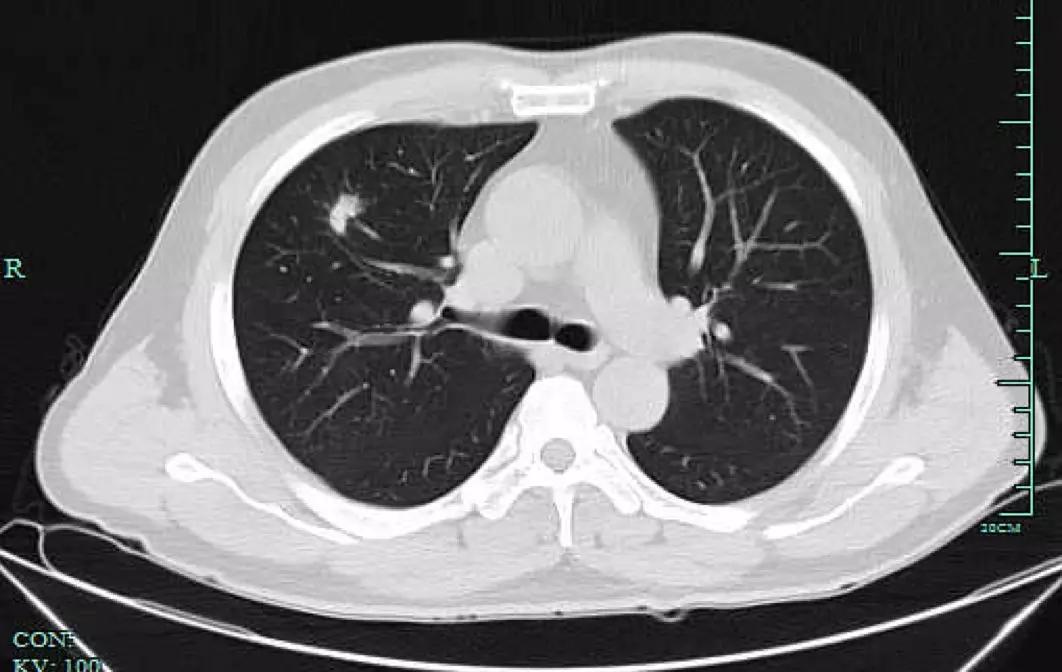

但也许是因为太拼了,章女士忽略了自己的身体变化。前年7月,章女士开始咳嗽,“是那种干咳,也没有流鼻涕没有喉咙痛,应该不是感冒。”她回忆,因为咳得实在难受就想去社区医院配点药,但医生建议她最好去大医院检查一下。章女士便来到浙大一院就诊并预约了检查,拿到体检结果那一刻她却直冒汗,“CT结果说我两侧的肺上都有磨玻璃小结节,右肺上叶的已经有1厘米大了,首先考虑是肺癌,我吓都吓‘死’了。”

肺结节是肺癌筛查中最常发现的类圆形、密度增高的肺部阴影。如果从大小来看,直径小于5毫米的叫做微小结节,直径在5毫米至10毫米的叫做肺小结节,小于3厘米的为肺结节,而如果直径大于3厘米就是肿块了。

磨玻璃样结节

磨玻璃样结节是指肺内密度轻微增加,呈模糊的云雾状,但仍能通过病灶看到其内部血管和支气管纹理,就好像透过磨玻璃视察一样。

实性结节

实性结节是指肺内圆形或类圆形高密度阴影,在CT下显现白色的影子,足以掩盖它走行的血管和支气管。实性结节的良恶性较难鉴别,有时候很难光凭一张CT来判断,医生需要充分了解病人的既往病史,比如是否有过肺结核、肺炎、其他肿瘤性疾病等,必要的时候,可以通过PET-CT,肺穿刺,甚至微创手术切除等方式明确诊断。